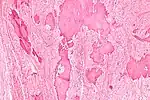

Low magnification micrograph of a calcified ovarian fibroma in the context of nevoid basal cell carcinoma syndrome. H&E stain. | |

On gross pathology, they are firm and white or tan. On microscopic examination, there are intersecting bundles of spindle cells producing collagen.

There may be thecomatous areas (fibrothecoma). The presence of an ovarian fibroma can cause ovarian torsion in some cases.

Diagnosis is usually made by ultrasonography showing a solid ovarian lesion, or, on some occasions, mixed tumors with solid and cystic components.[1] Computed tomography and magnetic resonance imaging can also be used to diagnose fibromas. In a series of 16 patients, 5 (28%) showed elevated levels of CA-125.[1] Histopathology demonstrates spindle-shaped fibroblastic cells and abundant collagen.[3]